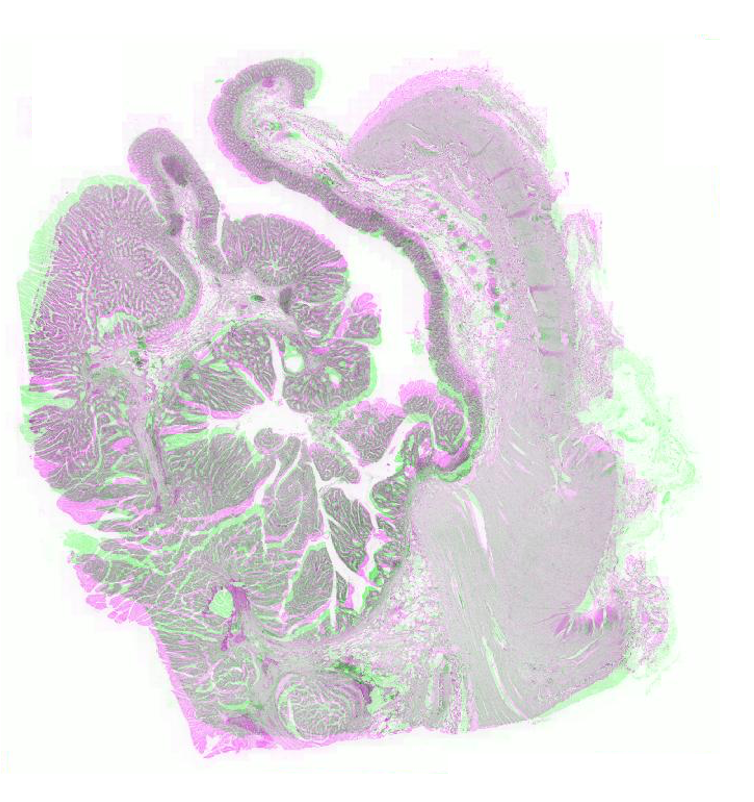

FigureΒ 2 shows the registration results for pathology images where we show the reference and floating images alongwith the misalignment images before registration and after registration using SR-Net and SR-Net. The misalignment is greatly reduced after registration using SR-Net while in the case of SR-Net there is still some resulting misalignment. This error can have significant consequences in the final diagnosis workflow. Hence the advantages of self-supervised segmentation maps are quite clear.

![]() |

| (a) | (b) | (c) | (d) | (e) |